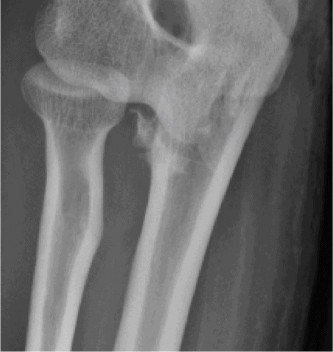

Identify the muscles that compose the force couples in the transverse and coronal planes? CASE 3 A 35-year-old male has had left shoulder pain for 4 months, ever since a low-speed motor vehicle accident (MVA). Physical examination demonstrates preserved range of motion but pain and some weakness with Jobe’s testing. His imaging is shown in Figure 2–8.

Figure 2–8_Reproduced with permission from Stadnick ME. _Partial Rotator Cuff Tears. MRI Web Clinic. 2007 (Apr).

What is the most likely diagnosis?

- Partial articular surface tendon avulsion (PASTA)

- Full-thickness rotator cuff tear

- Superior labrum anterior to posterior tear (SLAP)

- Anterior labral periosteal sleeve avulsion (ALPSA)

Discussion

The correct answer is (A). These are best diagnosed on an MRI as seen in the imaging provided; addition of intra-articular contrast can further improve this study. Answer B, full-thickness rotator cuff tear, is incorrect as the bursal side of the tendon can be seen to be in continuity. Answer C, a SLAP lesion, will be visualized as a labral tear on a coronal MRI and will be found at the biceps root. Answer D, an ALPSA lesion, will be most clearly seen on an axial MRI. It is a variant of a Bankart lesion where the labrum is displaced medially and inferiorly rolling down the glenoid neck underneath the periosteum.